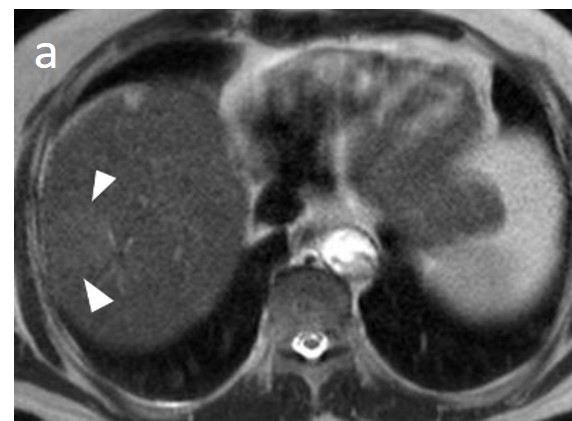

As mentioned before, the radiological hallmark that enables a confident non-histological diagnosis of HCC is the combination of hypervascularity on the arterial phase and hypoperfusion on the portal phase; as with CT, this “wash-in/wash-out” pattern is indispensable on MRI as well. According to the LI-RADS criteria, no lesion without hyperenhancement on the arterial phase can be definitely characterized as HCC; hyperenhancement has to be “non-rim”, i.e., not predominantly peripheral (in order to differentiate from metastases or cholangiocarcinoma) [51]. However, up to 40% of HCCs show no hypervascularity on the arterial phase, and these mainly represent early or poorly-differentiated HCCs [131,132]. Moreover, 40–60% of small HCCs lack wash-out during the portal phase [133,134] (Figure 10). Additional major and ancillary features are employed to help characterize the lesion and assign a LI-RADS category to it.

Figure 10. Evolution of a cirrhotic nodule into HCC. No suspicious lesions are identified on the T2 (a) and DWI (b) sequence of this 66-year-old man with cirrhosis due to hepatitis B infection. On the follow-up scan, performed 3 months later, increased T2 signal (c) is now observed in a nodule in segment V, which is associated with diffusion restriction (arrow) (d). After contrast administration, arterial enhancements (e) without delayed wash-out (f) are seen; absence of wash-out is frequent in early HCCs.